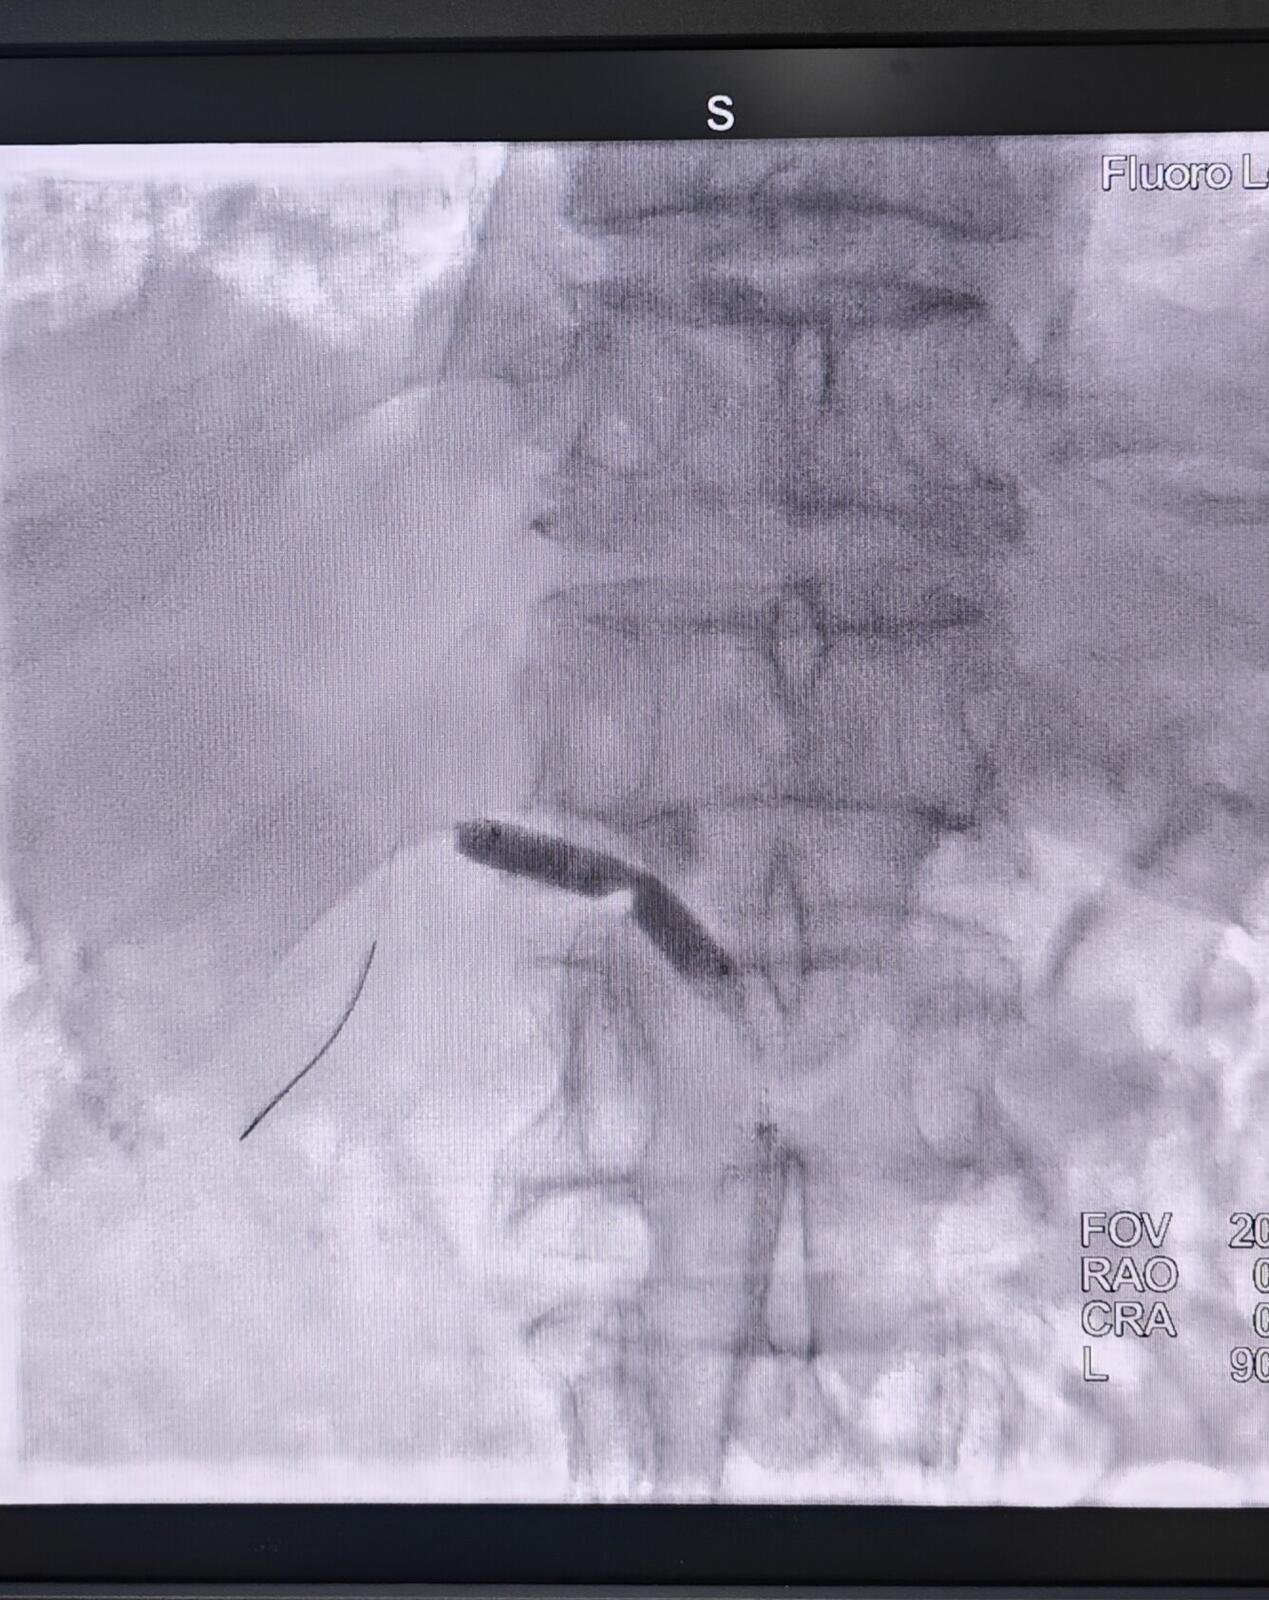

→_→肾动脉介入治疗过程:取仰卧位,常规消毒、铺无菌巾,局麻后穿刺股动脉并置入血管鞘。于患者的第1腰椎处放置猪尾导管行腹主动脉造影明确患者的肾动脉开口以及狭窄的情况。然后通过Cobra导管,进而选择肾动脉造影,从而使狭窄的程度、狭窄的部位、长度以及狭窄段两端正常RA的管腔直径得以明确。利用专用导丝和导管将选好的球囊和支架送到发生病变的位置,球囊扩张后准确释放支架。